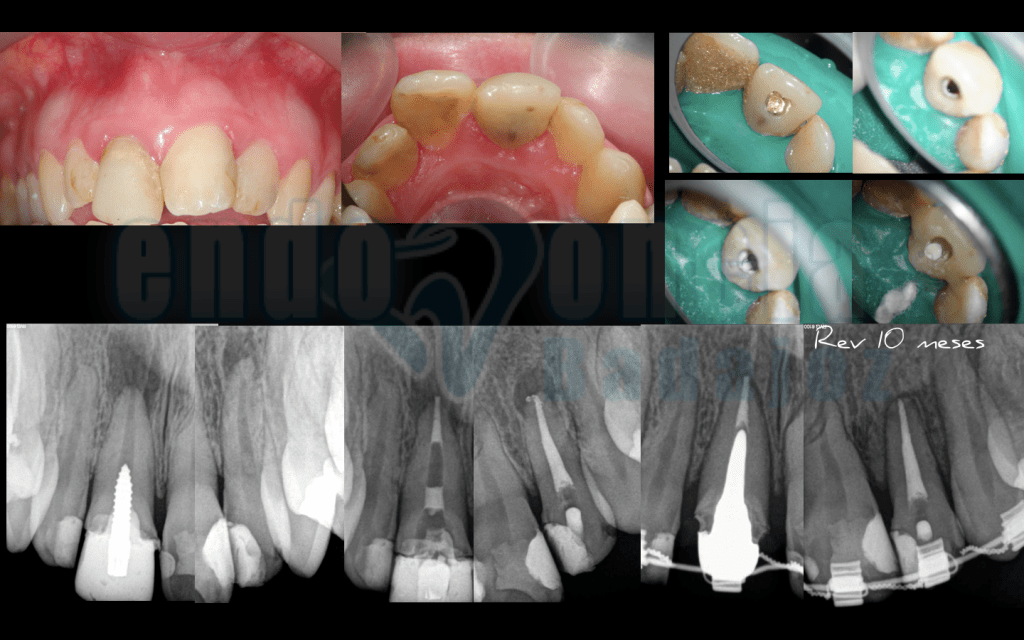

Caso 5:

Sector anterosuperior, tratamiento de un incisivo central con perno de aleación de oro, que decidimos eliminar para tratar el conducto y sellarlo con MTA y un I. lateral , ambos con lesiones apical que a los 10 meses vemos con perfecto estado de salud apical.

Captura de pantalla 2015-12-08 a las 11.26.58